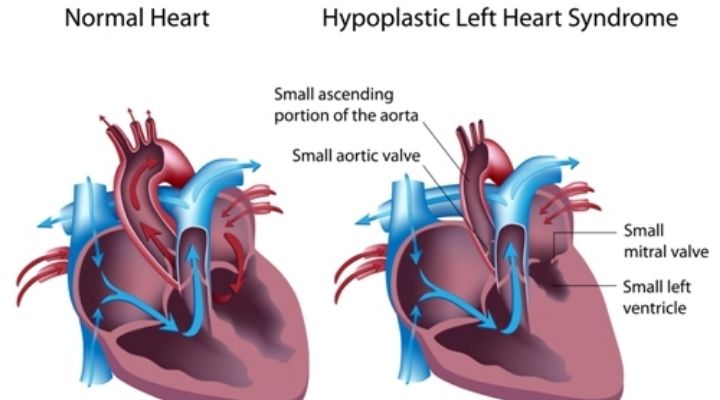

Doctors ended up discovering that Jill had a congential condition that was unknown. This condition is what caused her heart to stop beating int he first place and led to her going into a coma.

Out Of Her Coma

Jill had come out of her coma and was breathing on her own. By a miracle of God, she underwent surgery to implant a pacemaker for her heart condition and then went into a rehabilitation center.